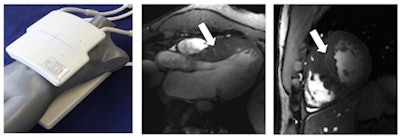

Left: Picture of the 16-channel transmit/receive radiofrequency antenna designed and developed for this 7-tesla cardiac MRI study. Middle: Three-chamber view of the heart of a patient with hypertrophic cardiomyopathy shows subtle myocardial crypts highlighted by the white arrow. Image was acquired at 7 tesla. Right: Short-axis view of the heart of a patient with hypertrophic cardiomyopathy showing myocardial crypts highlighted by the white arrow. Image was acquired at 7 tesla. Images courtesy of Thoralf Niendorf, PhD.After screening 131 patients with hypertrophic cardiomyopathy between 2011 and 2014, researchers chose 13 patients (mean age of 56 years, ± 31 years) and 13 healthy age- and gender-matched control subjects (mean age of 55, ± 31 years) who met the study criteria.